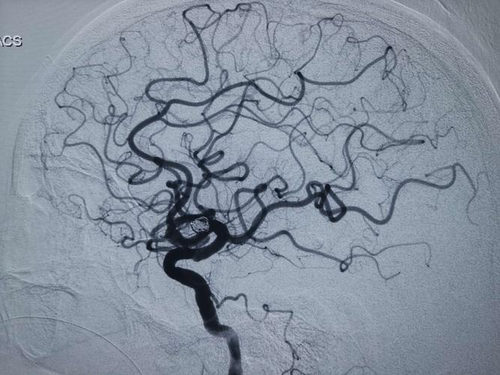

2、神经系统定位征兆脑栓塞主要发生在脖子部位的内部动脉系统,尤其是患者的大脑中动脉是发病的主要位置。栓子的数量以及范围和位置决定了病情的严重程度,急性发作时可能出现头痛,头晕或局部疼痛。大约有一半的患者在发病时有意识影响,但持续时间很短。